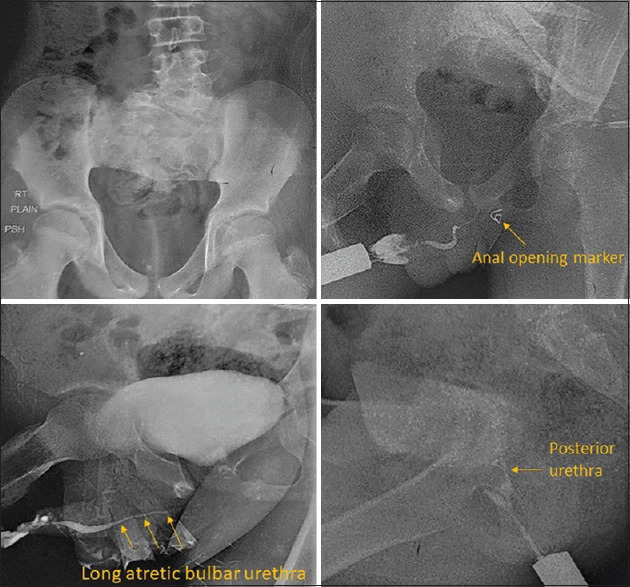

尿道重复是一种罕见的先天性异常,其特征是有多个尿道通道,具有不同的路线、外部开口的位置和表现。表现可以是多种多样的,取决于个人的解剖分配,但大多数表现为梗阻,复发性尿路感染,或双尿流。治疗取决于复制的类型和相关的异常。在此,我们报告一例不符合任何已知类型的尿道重复形式的病例,在肛门边缘有五个开口。

Urethral duplication is a rare congenital anomaly characterized by more than one urethral channel, with varied course, location of the external opening, and presentation. Presentations can be varied, depending upon individual anatomical dispensation but mostly present as obstruction, recurrent urinary infection, or double urinary stream. Treatment depends on the type of duplication and associated anomalies. Here, we report a case of urethral duplication which did not fit into any known reported type of urethral duplication forms and had five openings at the anal verge.